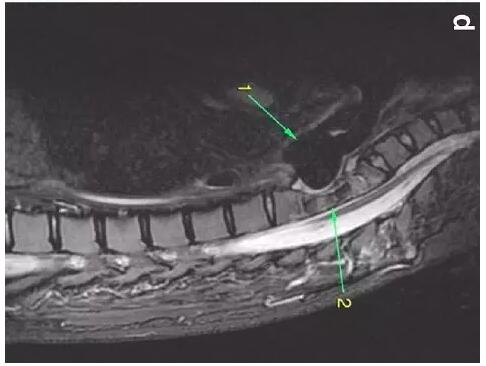

患者入住我院前行胸MRI已經(jīng)發(fā)現(xiàn)類似表現(xiàn)(圖d),當時診斷為骨髓炎。

下圖箭頭1為氣切套管氣囊緊貼T1-4椎體水平,造成椎體前部受到侵蝕(箭頭2):